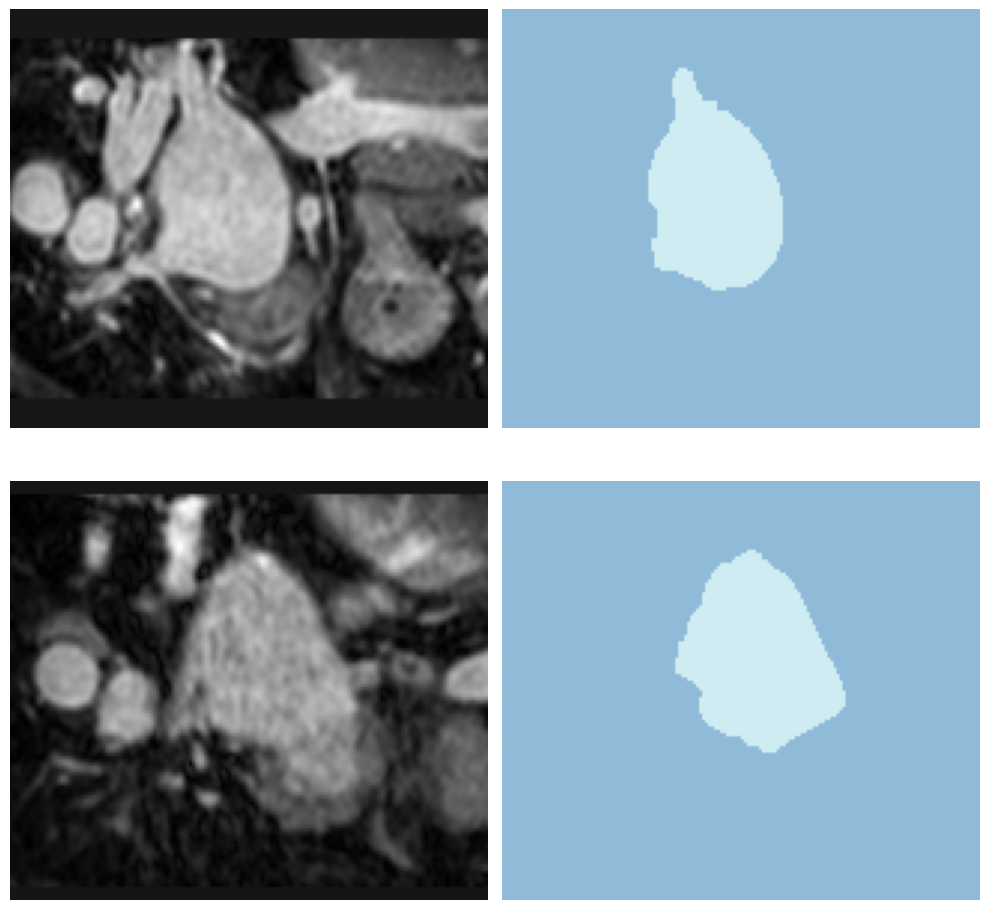

dls.show_batch(anatomical_plane=2)

learn.show_results(anatomical_plane=1)

learn.load('heart-weights');test_dl = learn.dls.test_dl(test_df,with_labels=True)test_dl.show_batch(anatomical_plane=0, figsize=(10,10))

learn.show_results(anatomical_plane=0, dl=test_dl)